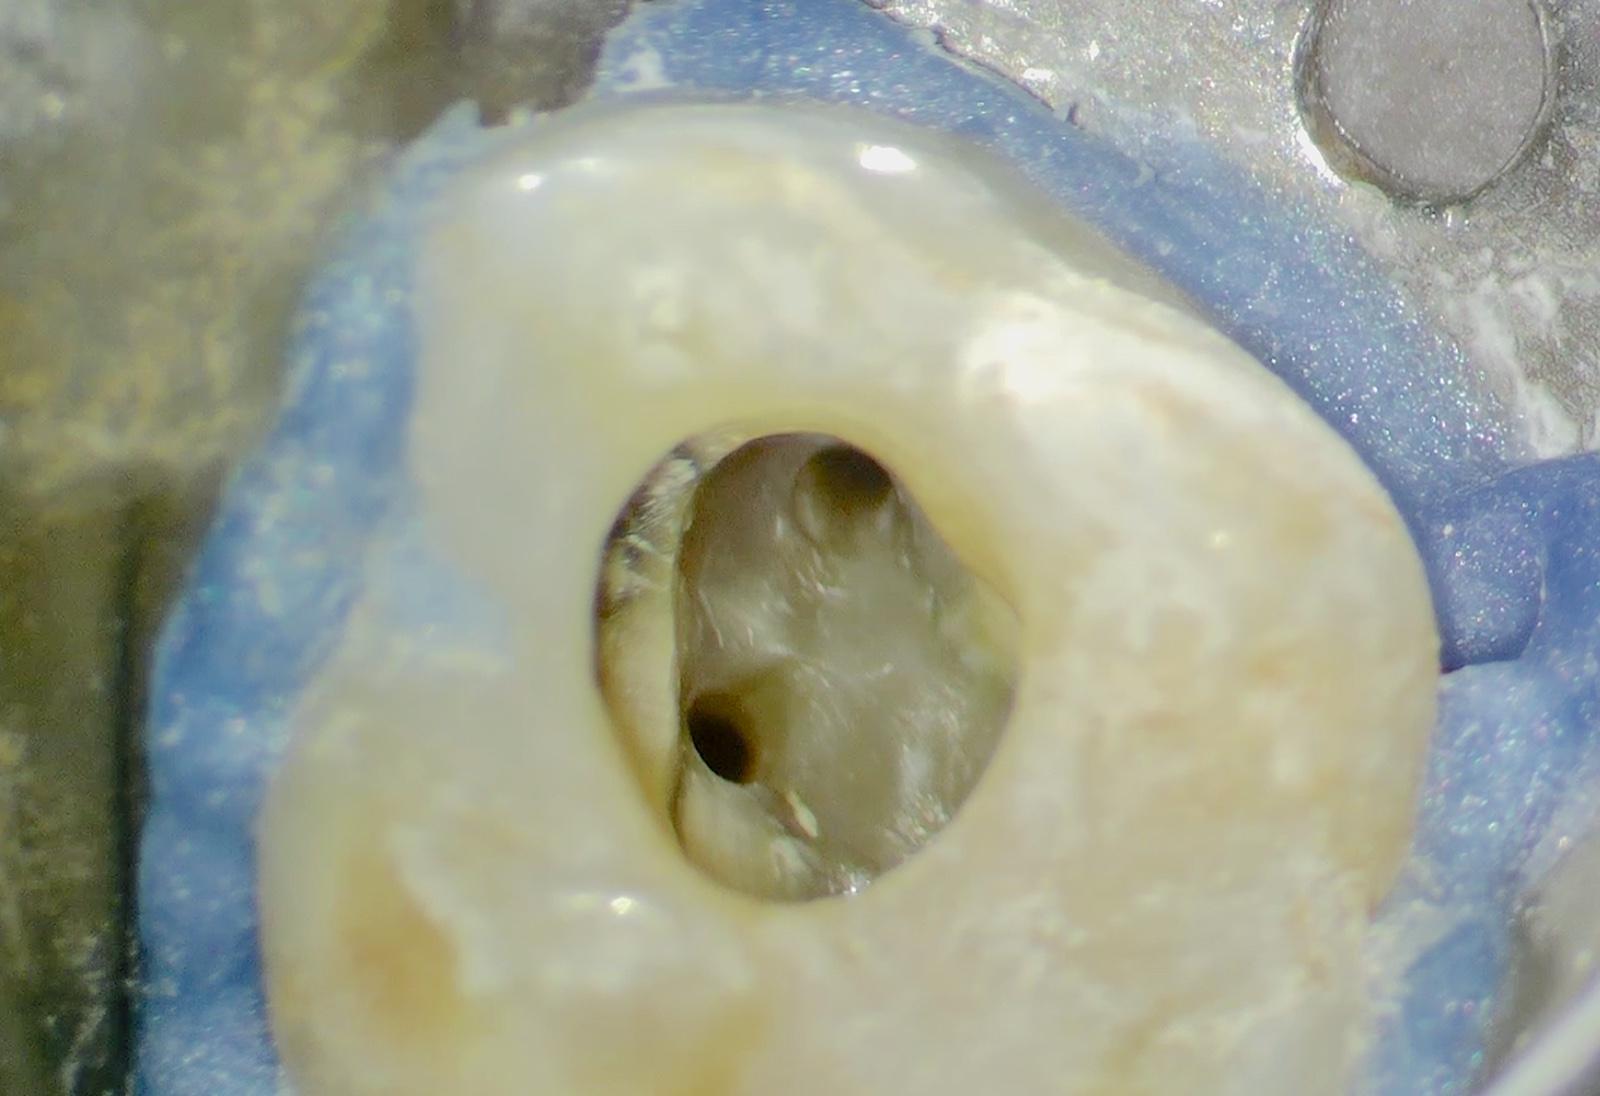

Locating the Hidden Anatomy: Due to heavy calcification, ultrasonic tips were used.

Successfully located the MB1 and the extremely narrow MB2 canal under magnification.